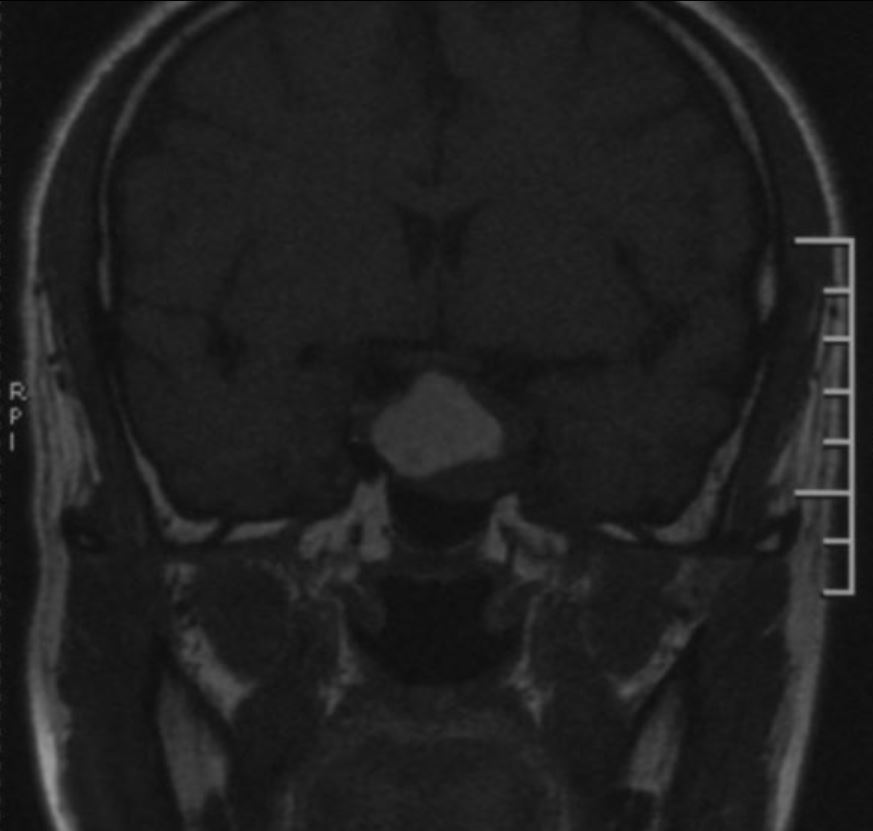

鞍区磁共振检查发现:鞍区肿瘤卒中可能,肿瘤侵犯双侧海绵窦、颈内动脉,鞍隔被顶起,鞍底部分塌陷。复旦大学附属肿瘤医院神经外科高阳

矢状位增强